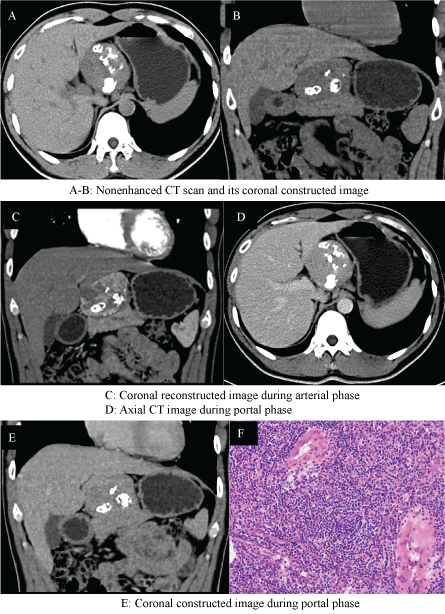

A 32-year-old man was referred to us with an abdominal mass detected by ultrasonographic examination during phyisical checkup. She had history of hepatic hemangioma for 10 years. Examination of the heart and lungs was normal, and there were no apparent enlarged lymph nodes. The tumor markers were all within normal range. Subsequently, the CT of the abdomen confirmed the presence of a well circumscribed, encapsulated mass with different shaped calcifications, which seemed to arise from the pancreas and was adherent to the pancreatic neck. The mass enhanced intensely in the arterial phase with moderate washout in the venous phase. In addition, CT revealed no other enlarged lymph nodes and involved organs (Figure 1(A-E)). At exploratory laparotmy, an encapsulated tumor measuring 6 × 7 cm was completely removed adjacent to the pancreatic neck. Pathology revealed Castleman lymphadenopathy of hyaline-vascular type (Figure 1F). The patient was discharged 7 days later without postoperative complications and is well 2 years after surgery.

Figure 1: (A-E) CT scan shows a well-circumscribed, round, multiple-calcified mass that appears intensely enhanced in the arterial phase with moderate washout in the venous phase; (F) Histolopathological examination shows a hyperplastic lymph node with large follicles, marked vascular proliferation and hyalinization of the germinal centers.